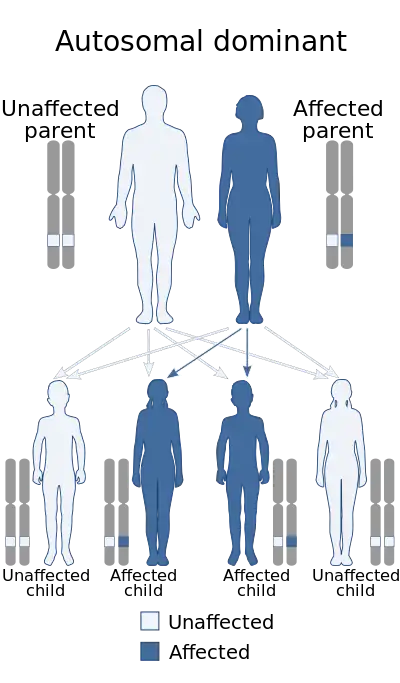

| Parkes Weber syndrome is inherited in an autosomal dominant manner. | |

In the body, the vascular system consists of arteries, veins and capillaries. When abnormalities such as vascular malformation, capillary arteriovenous malformations (AVMs), arteriovenous fistulas (AVFs) and overgrowth of a limb occur together in combination and disturb the complex network of blood vessels of the vascular system, it is known as PWS.[5] The capillary malformations and AVFs are known to be present from the birth. In some cases, PWS is a genetic condition where the RASA1 gene is mutated and displays an autosomal dominant inheritance pattern.[6] If PWS is genetic then most patients show multiple capillary malformations. Patients who do not have multiple capillary malformations most likely did not inherit PWS and do not have RASA1 mutations. In such cases, the cause of PWS is often unknown and is sporadic as most cases often are.

The causes for PWS are either genetic or unknown. Some cases are a direct result of the RASA1 gene mutations. And individuals with RASA1 can be identified because this genetic mutation always causes multiple capillary malformations.[12] PWS displays an autosomal dominant pattern of inheritance.[6] This means that one copy of the damaged or altered gene is sufficient to elicit PWS disorder. In most cases, PWS occurs in people that have no family history of the condition. In such cases the mutation is sporadic. And for patients with PWS with the absence of multiple capillary mutations, the causes are unknown.